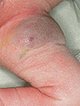

Bereits unmittelbar nach Embolisation ist der Tumor in der Farbe deutlich blasser geworden, auch das Volumen hat deutlich abgenommen als Zeichen der Involution, die durch die Embolisation mit Ausschalten der Vaskularisation induziert wurde.

Auf eine zunächst geplante zusätzliche operative Resektion der Tumorreste wurde aufgrund des guten Ergebnisses verzichtet. Der weitere Verlauf wird abgewartet.

Im weiteren Verlauf nach der Embolisation hat der Tumor stark an Volumen abgenommen, er ist jetzt nicht mehr erhaben und asymptomatisch.

Foto im Alter von 4 Jahren 8 Monaten. Als Rest des NICH ist lediglich noch eine lokale bläuliche Dyskoloration der Haut zu sehen.